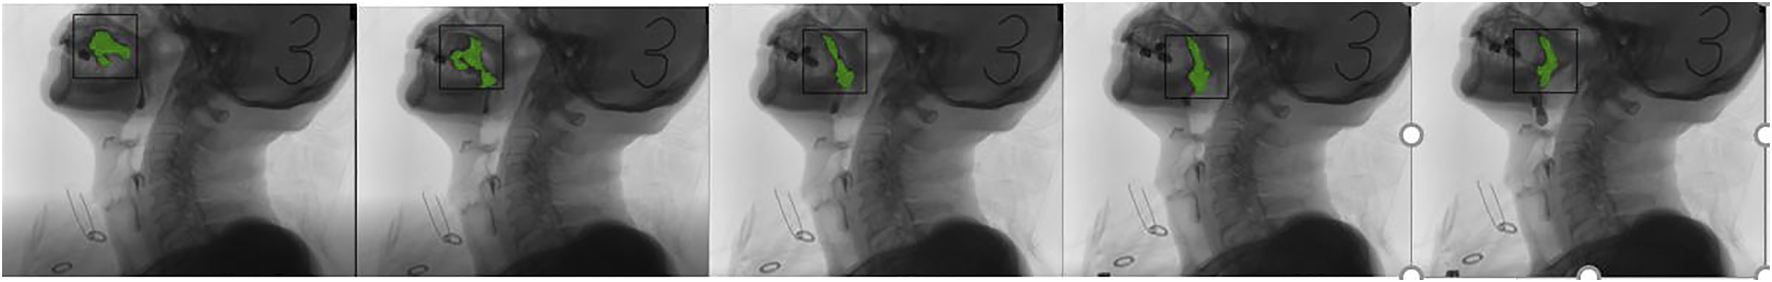

The tracking effect of the algorithm in this paper is as follows:

It can be clearly observed from Figure 10 that occlusion occurs, but the tracker does not lose the target position. With the body leaning forward, the tracking frame can also track the target very well.

FIGURE 10. Filtering results. (1) The swallowing stage of the oral cavity; (2) the tracking target is the palate; and (3) Have obvious occlusion; (4) The target is not lost; (5) and (6) Occlusion occurs again; Occlusion and forward leaning; (8) and (9) Barium meal interference; (10) and (11) Barium meal is swallowed into the throat; (12) End of swallowing.